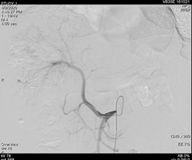

遂继续以碘油4 ml+0.9%氯化钠20 ml+吡柔比星20 mg+雷替曲塞2支方案,行第二次TACE治疗。

图片

图:第二次TACE治疗